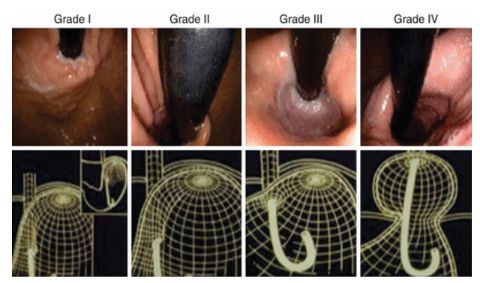

Đặc điểm của NVDD-TQ theo phân độ Hill được đánh giá như hình 1. (A) Độ I: nếp gấp rõ, lỗ tâm vị ôm chặt ống soi. (B) Độ II: nếp gấp còn rõ nhưng không bằng độ I, lỗ tâm vị mở ra đóng vào nhanh theo hô hấp. (C) Độ III: nếp gấp không rõ và lỗ tâm vị không ôm chặt ống soi. (D) Độ IV: không còn nếp gấp, vùng nối dạ dày thực quản mở và có thể thấy được biểu mô thực quản ở tư thế quặt ngược ống soi ở dạ dày.

(A) Độ I: nếp gấp rõ, lỗ tâm vị ôm chặt ống soi. (B) Độ II: nếp gấp còn rõ nhưng không bằng độ I, lỗ tâm vị mở ra đóng vào nhanh theo hô hấp. (C) Độ III: nếp gấp không rõ và lỗ tâm vị không ôm chặt ống soi. (D) Độ IV: không còn nếp gấp, vùng nối dạ dày thực quản mở và có thể thấy được biểu mô thực quản ở tư thế quặt ngược ống soi ở dạ dày.

Nội soi thực quản, dạ dày tá tràng - Esophagogastroduodenoscopy (EGD) là phương pháp đánh giá tiêu chuẩn để kiểm tra đường tiêu hóa trên. Khả năng của hàng rào chống trào ngược cơ học có thể được đánh giá nội soi theo hai cách; một cách là đo chiều dài trục của bất kỳ khối thoát vị khe hoành nào hiện diện (giữa khe thoát vị và khớp nối dạ dày thực quản). Do động học sinh lý ở khu vực này, có thể khó đo chiều dài của khối thoát vị khe hoành, ngay cả trong điều kiện lý tưởng. Không rõ độ dài mà thoát vị khe hoành khi nào sẽ trở nên có ý nghĩa lâm sàng, tức là có ý nghĩa bệnh lý, và vì GEJ không cố định, hầu hết các nhà nội soi sử dụng độ dài 2 cm ngưỡng chẩn đoán giữa bình thường và bất thường. Một cách khác để đánh giá GEJ là phân loại nếp van dạ dày thực quản (GEFV) sử dụng phân loại Hill . Các nghiên cứu đã chỉ ra mối liên quan giữa thang điểm Hill và tần suất GERD. Phân độ Hill ở mức cao cũng liên quan đến áp lực cơ vòng thực quản dưới thấp, tăng tần suất thoát vị khe hoành và có khả năng dự đoán đáp ứng kém với điều trị bằng thuốc ức chế bơm proton. Phân loại Hill đã được chứng minh là phù hợp, hữu ích và cung cấp thông tin hữu ích khi đánh giá bệnh nhân nghi ngờ mắc bệnh lý GERD. Viêm thực quản có thể được xác định bằng nội soi và phân loại theo phân loại Los Angeles (LA).